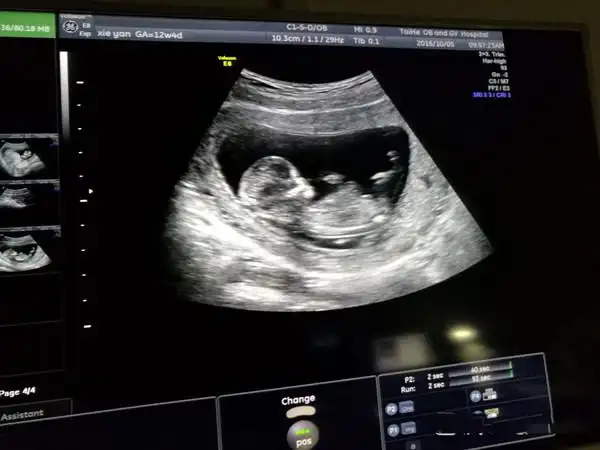

这是快十二周做的nt !这个亮点是不是说宝宝是男孩的记录大啊?

有人说nt检查看生男生女很准的,说是怀孕12周做nt检查已经看到小丁丁

孕12周nt检查显示有三个亮点是男孩还是女孩

不乱收费!nt三个亮点是男孩女孩"备孕成功"-第1张图片-吉泽网

三个月做的nt 这是男孩还是女孩?